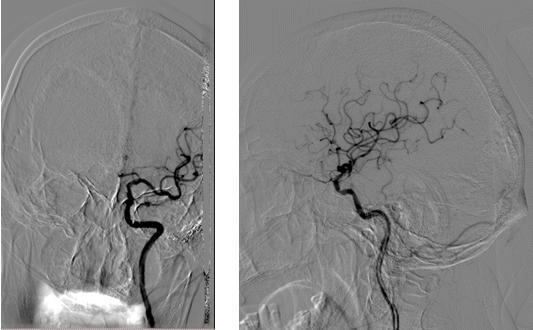

神经内科郝永岗副主任医师与神经血管介入团队充分讨论患者病情,完善术前相关检查及药物准备,排除禁忌症,决定为患者实施经皮左颈内动脉颅内段球囊扩张成形术。9月8日,我院神经血管介入团队在MRI-DSA杂交手术室于局部麻醉下为患者实施手术,历时70分钟,成功扩张成形病变血管,使脑血流明显改善,挽救了处于缺血状态的神经细胞,避免了梗死核心进一步扩大。术后经过神经内科及康复医学科联合积极治疗,胡大爷右侧肢体肌力明显增强。

(血管成形术后造影:狭窄解除,血流明显改善)